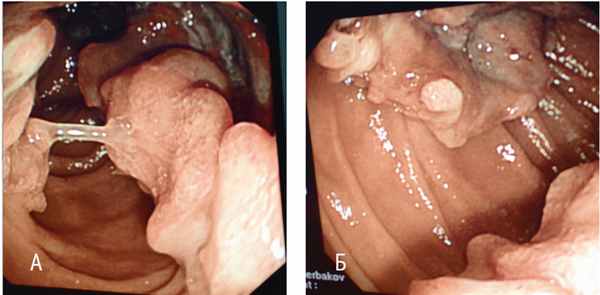

При проведении ЭГДС в нисходящем отделе двенадцатиперстной кишки по всем стенкам визуализированы опухолевидные разрастания с бугристой поверхностью бледно-розового цвета, местами с глубокими изъязвлениями, покрытыми фибрином. Просвет кишки в области опухоли сужен, деформирован, однако свободно проходим для аппарата. При инструментальной пальпации опухоль мягкой консистенции, контактная кровоточивость не определялась. Взята множественная биопсия. Заключение эндоскопического исследования: опухоль нисходящего отдела двенадцатиперстной кишки, предположительно метастаз меланомы ( рис. 2 ).

Рис. 2. Эндоскопическая картина беспигментной метастатической меланомы двенадцатиперстной кишки больной В., 44 лет. Фото авторов